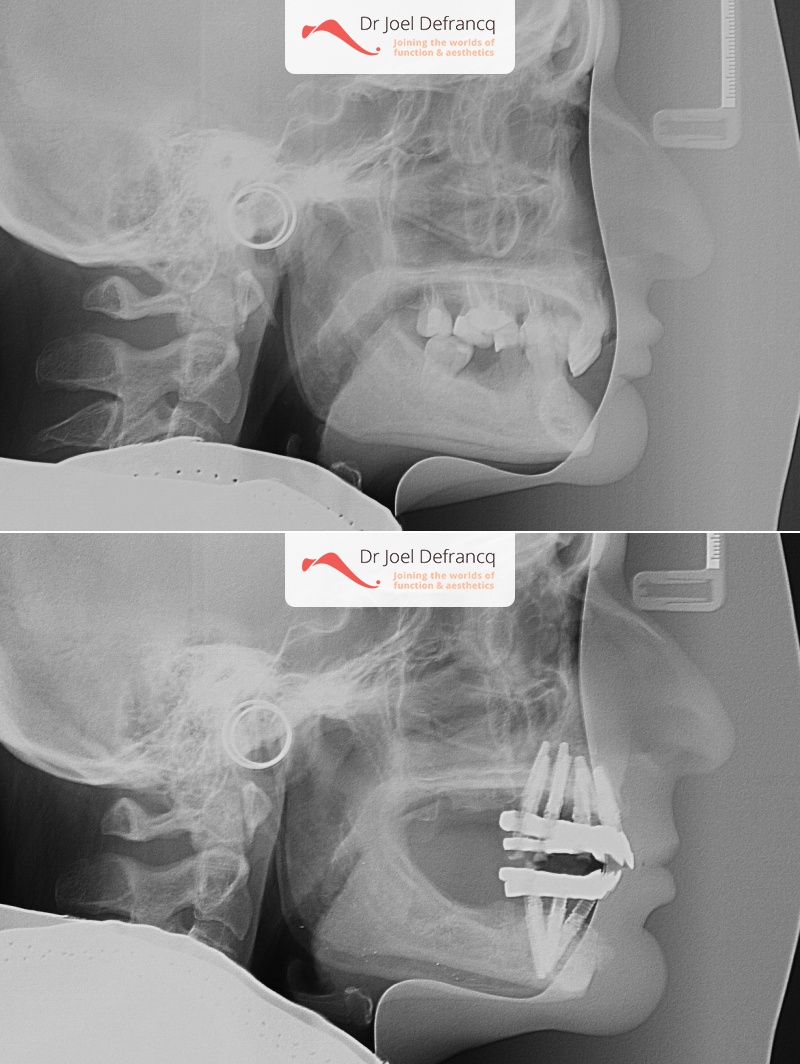

Balera: Extreme deep bite - implants

Diagnose van het gezicht

- Te kleine onderkaak (Overbeet)

Behandeling tandheelkundige implantaten

- Vaste tanden op implantaten (bovenkaak)

- Vaste tanden op implantaten (onderkaak)

- Implantaten met beenopbouw